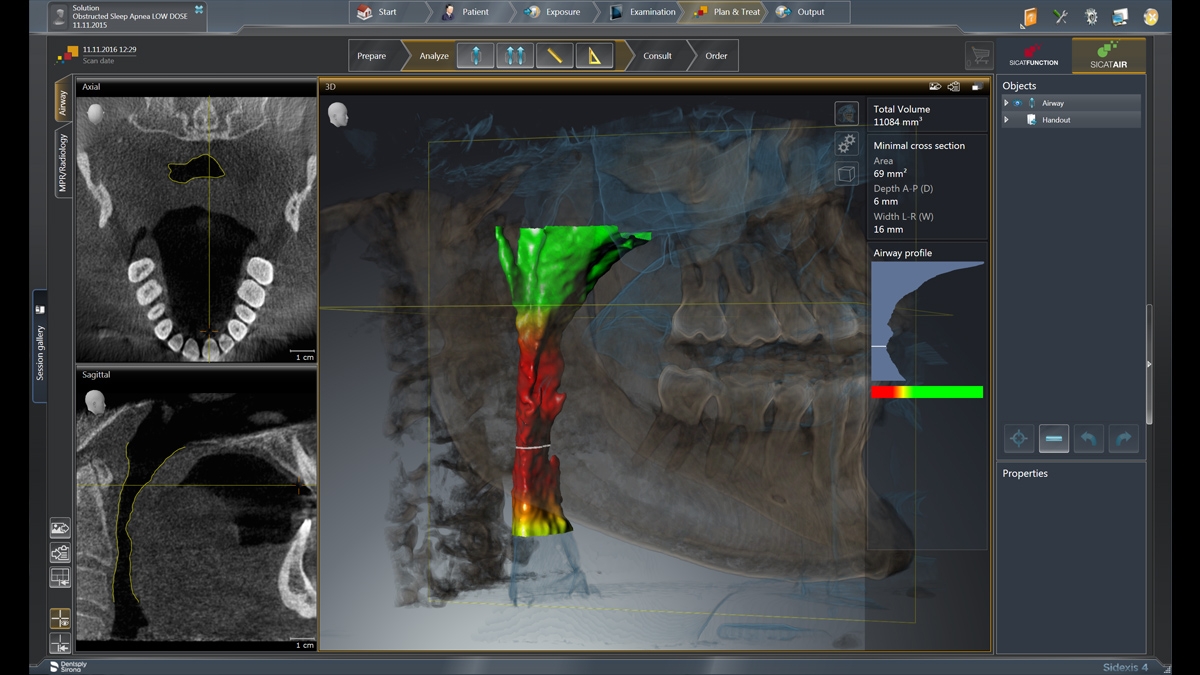

3D成像——亮点

3D解决方案一览

3D示例图

MARS——金属伪影消除软件

金属伪影是3D X射线成像的一大挑战。在三维重建过程中,不透射线的物体会产生阴影和拖尾效应,从而干扰检查结果。MARS自动减少金属伪影,方便诊断。